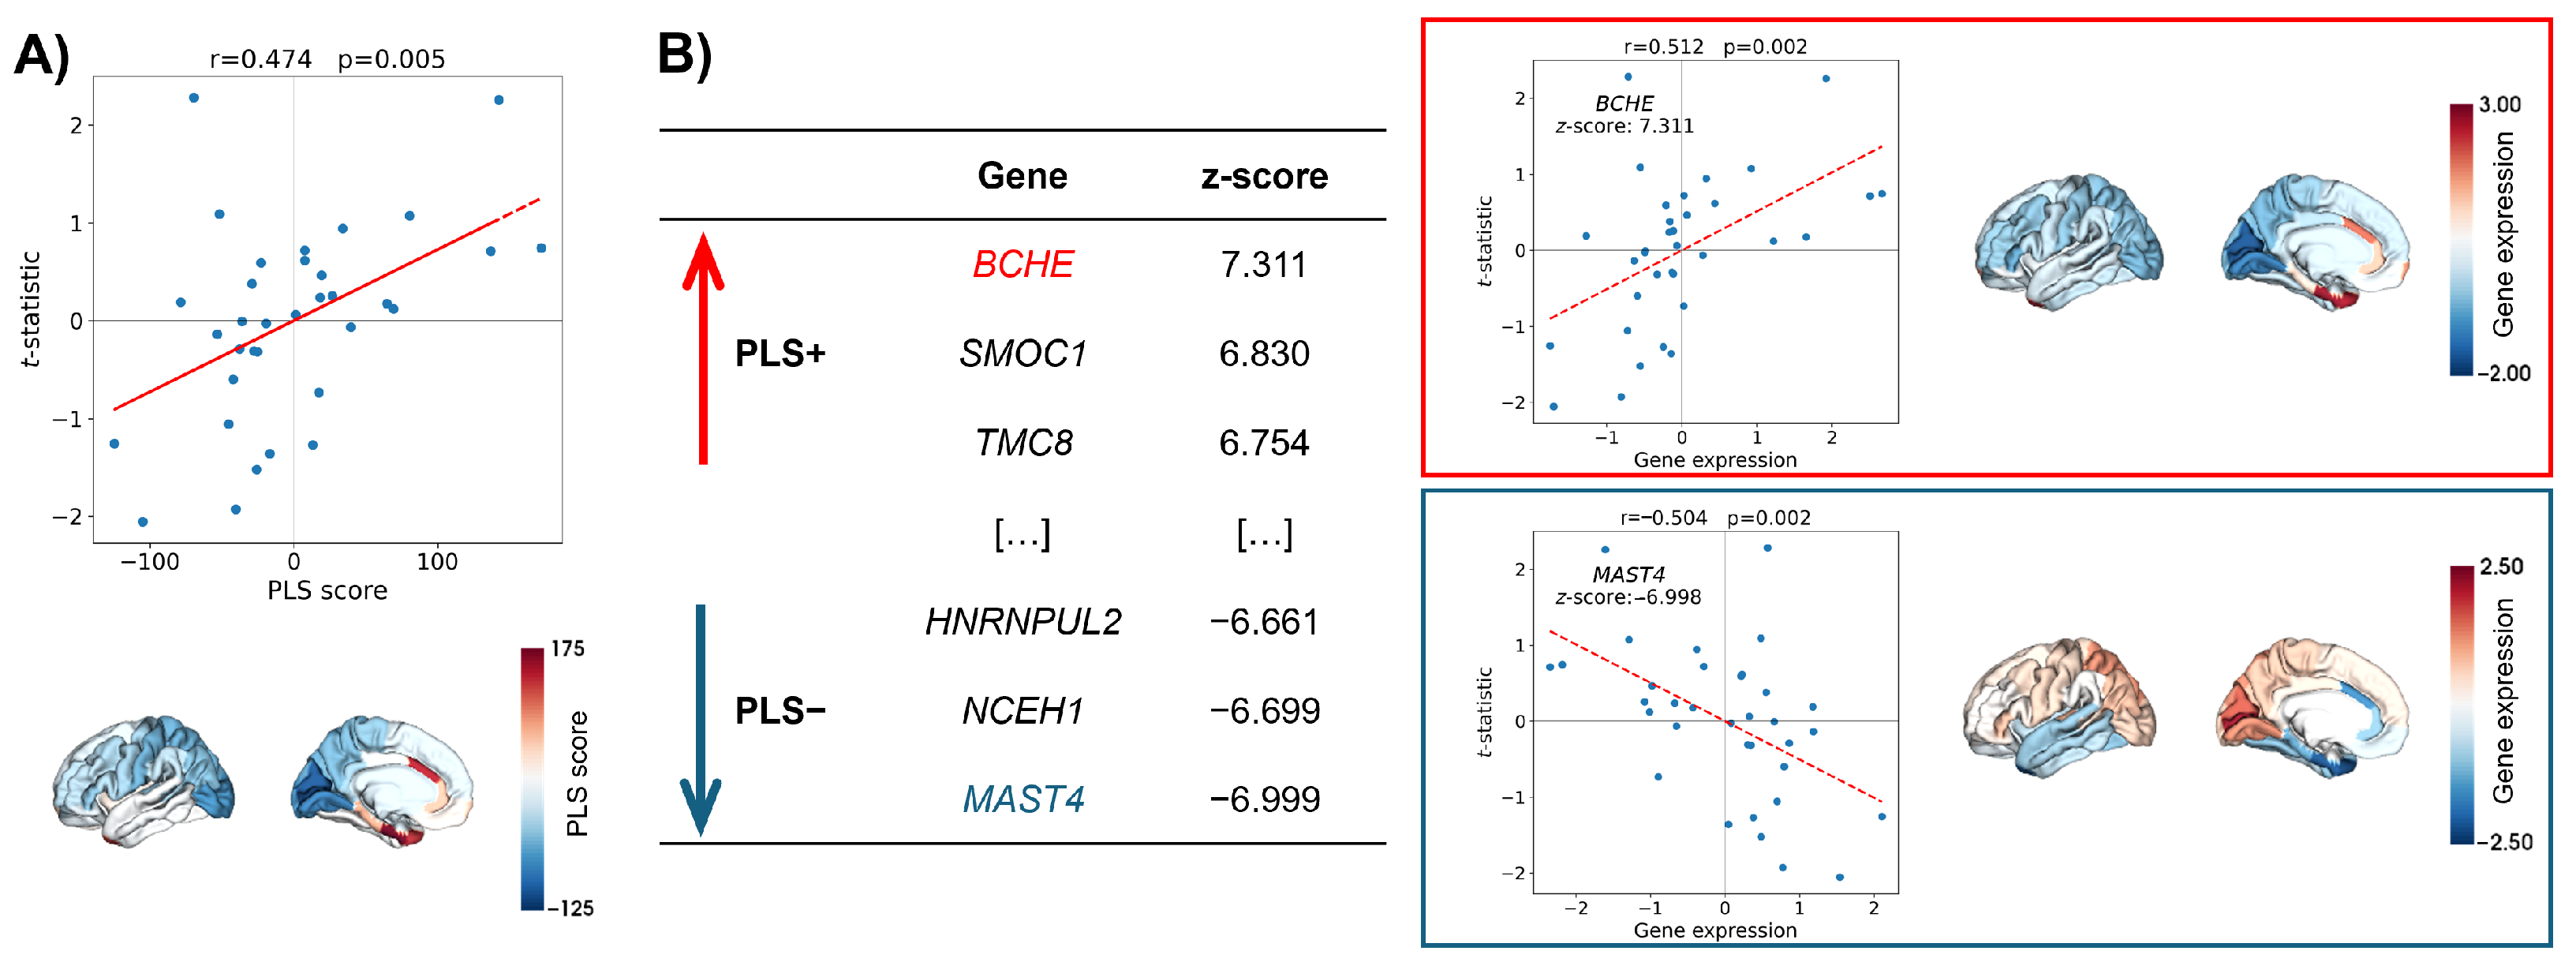

2.2. Regional Morphometric Similarity and Transcriptomics Relationship